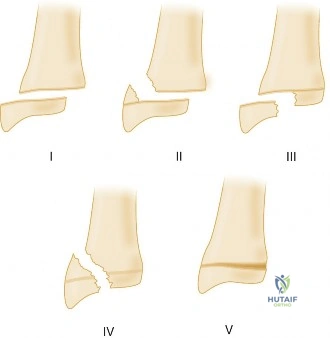

While buckle fractures are typically stable, certain findings necessitate a more rigid form of immobilization (e.g., short arm cast) or even operative intervention for other types of pediatric distal radius fractures:

- Complete Fracture: Any complete cortical breach, even with minimal displacement (e.g., greenstick fractures with significant angulation or potential for displacement).

- Significant Displacement or Angulation: Displaced metaphyseal fractures (>15-20 degrees angulation) or those with translational shift that may require reduction.

- Physeal Involvement (Salter-Harris types):

- Salter-Harris I: Often stable, but may require cast immobilization depending on clinical suspicion and mechanism.

- Salter-Harris II: Stable types can be managed with closed reduction and casting. Unstable or significantly displaced types may require pinning.

- Salter-Harris III, IV, V: These are intra-articular or complex physeal fractures requiring anatomical reduction, often surgically, to prevent growth disturbance or articular incongruity.

- Open Fractures: Require immediate surgical debridement and often fixation.